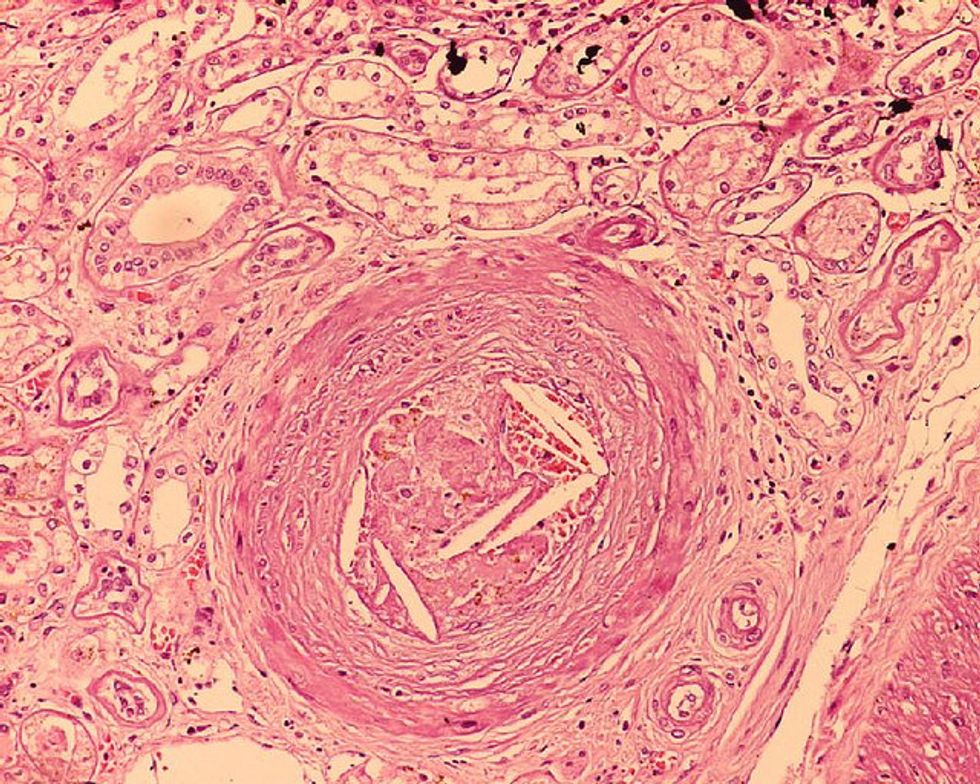

Photo: Cholesterol emboli in an interlobular artery. (Boonyarit Cheunsuchon, MD)